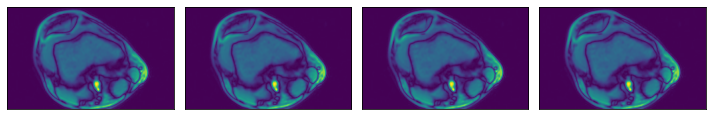

Higher dimensionality#

Numpy reader can also be used to load data of higher dimensionality (up to 6 dimensions). Let’s demonstrate with our 3D MRI arrays

[8]:

@pipeline_def(batch_size=batch_size, num_threads=3, device_id=0)

def pipe_3d():

data = fn.readers.numpy(

device="cpu", file_root=data_dir_3d, file_filter="*.npy"

)

return data

data_3d = run(pipe_3d())

for s in range(len(data_3d)):

print(f"Sample {s} shape: {data_3d[s].shape}")

# Displaying first 4 slices of the first sample in the batch

plot_batch(

[

data_3d[0][0, :, :],

data_3d[0][1, :, :],

data_3d[0][2, :, :],

data_3d[0][3, :, :],

]

Sample 0 shape: (5, 512, 512)

Sample 1 shape: (9, 512, 512)

Sample 2 shape: (2, 512, 512)

Sample 3 shape: (38, 320, 320)

../../../../_images/examples_general_data_loading_numpy_reader_pipeline_mode_16_1.png

Region-of-interest (ROI) API#

In the example shown above, we see that the relevant data is concentrated in the upper left quadrant of the image and the rest does not contain useful information. This is not true for all the images in the dataset, but it will serve us as a good example to demonstrate ROI reading.